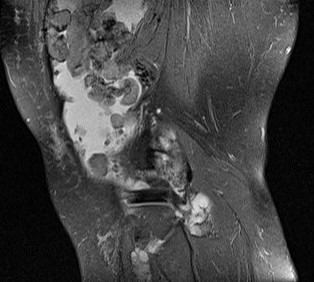

MRI

Synovial Proliferation

Soft tissue lesions same signal intensity as cartilage

Synovial chondromatosis

Synovial osteochondromatosis